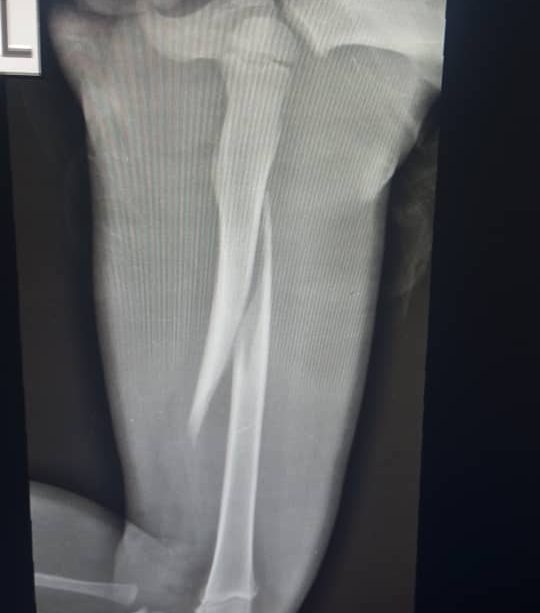

A three-year-old boy faces severe child abuse at the hands of his stepmother who allegedly fractured his thigh bone with a pestle.

He told me the wife of his opposite neighbour used pestle to break the lap bone of her 3yr old Step son yesterday evening Tears rolled down my eyes immediately…I asked what did the three year old old do to warrant using pestle to shatter his lap bone into two ???

I asked did you ask the little boy who did it and he said yes that the step mom beat him…my neighbour that saw me in the balcony Told me he was the one that broke into there house when he had the little boy cry in there flat upon arrival the boy couldn’t stand and leg was dangling legs and swollen foot.